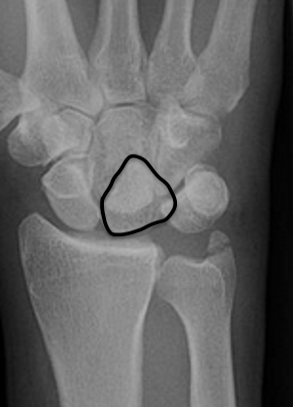

Gilula carpal arcs

Normally there are 3 smooth carpal arcs on PA xray

Arc I: Proximal cortical margins of proximal carpal row Arc II: Distal carpal margin of the proximal carpal row Arc III: Proximal cortices of the capitate and hamate |

AP X-ray

Disruption of Gilula's 3 smooth carpal arcs / triangular lunate

Normal versus disruputed Gilula's carpal arcs

Piece of pie / triangular appearance of lunate